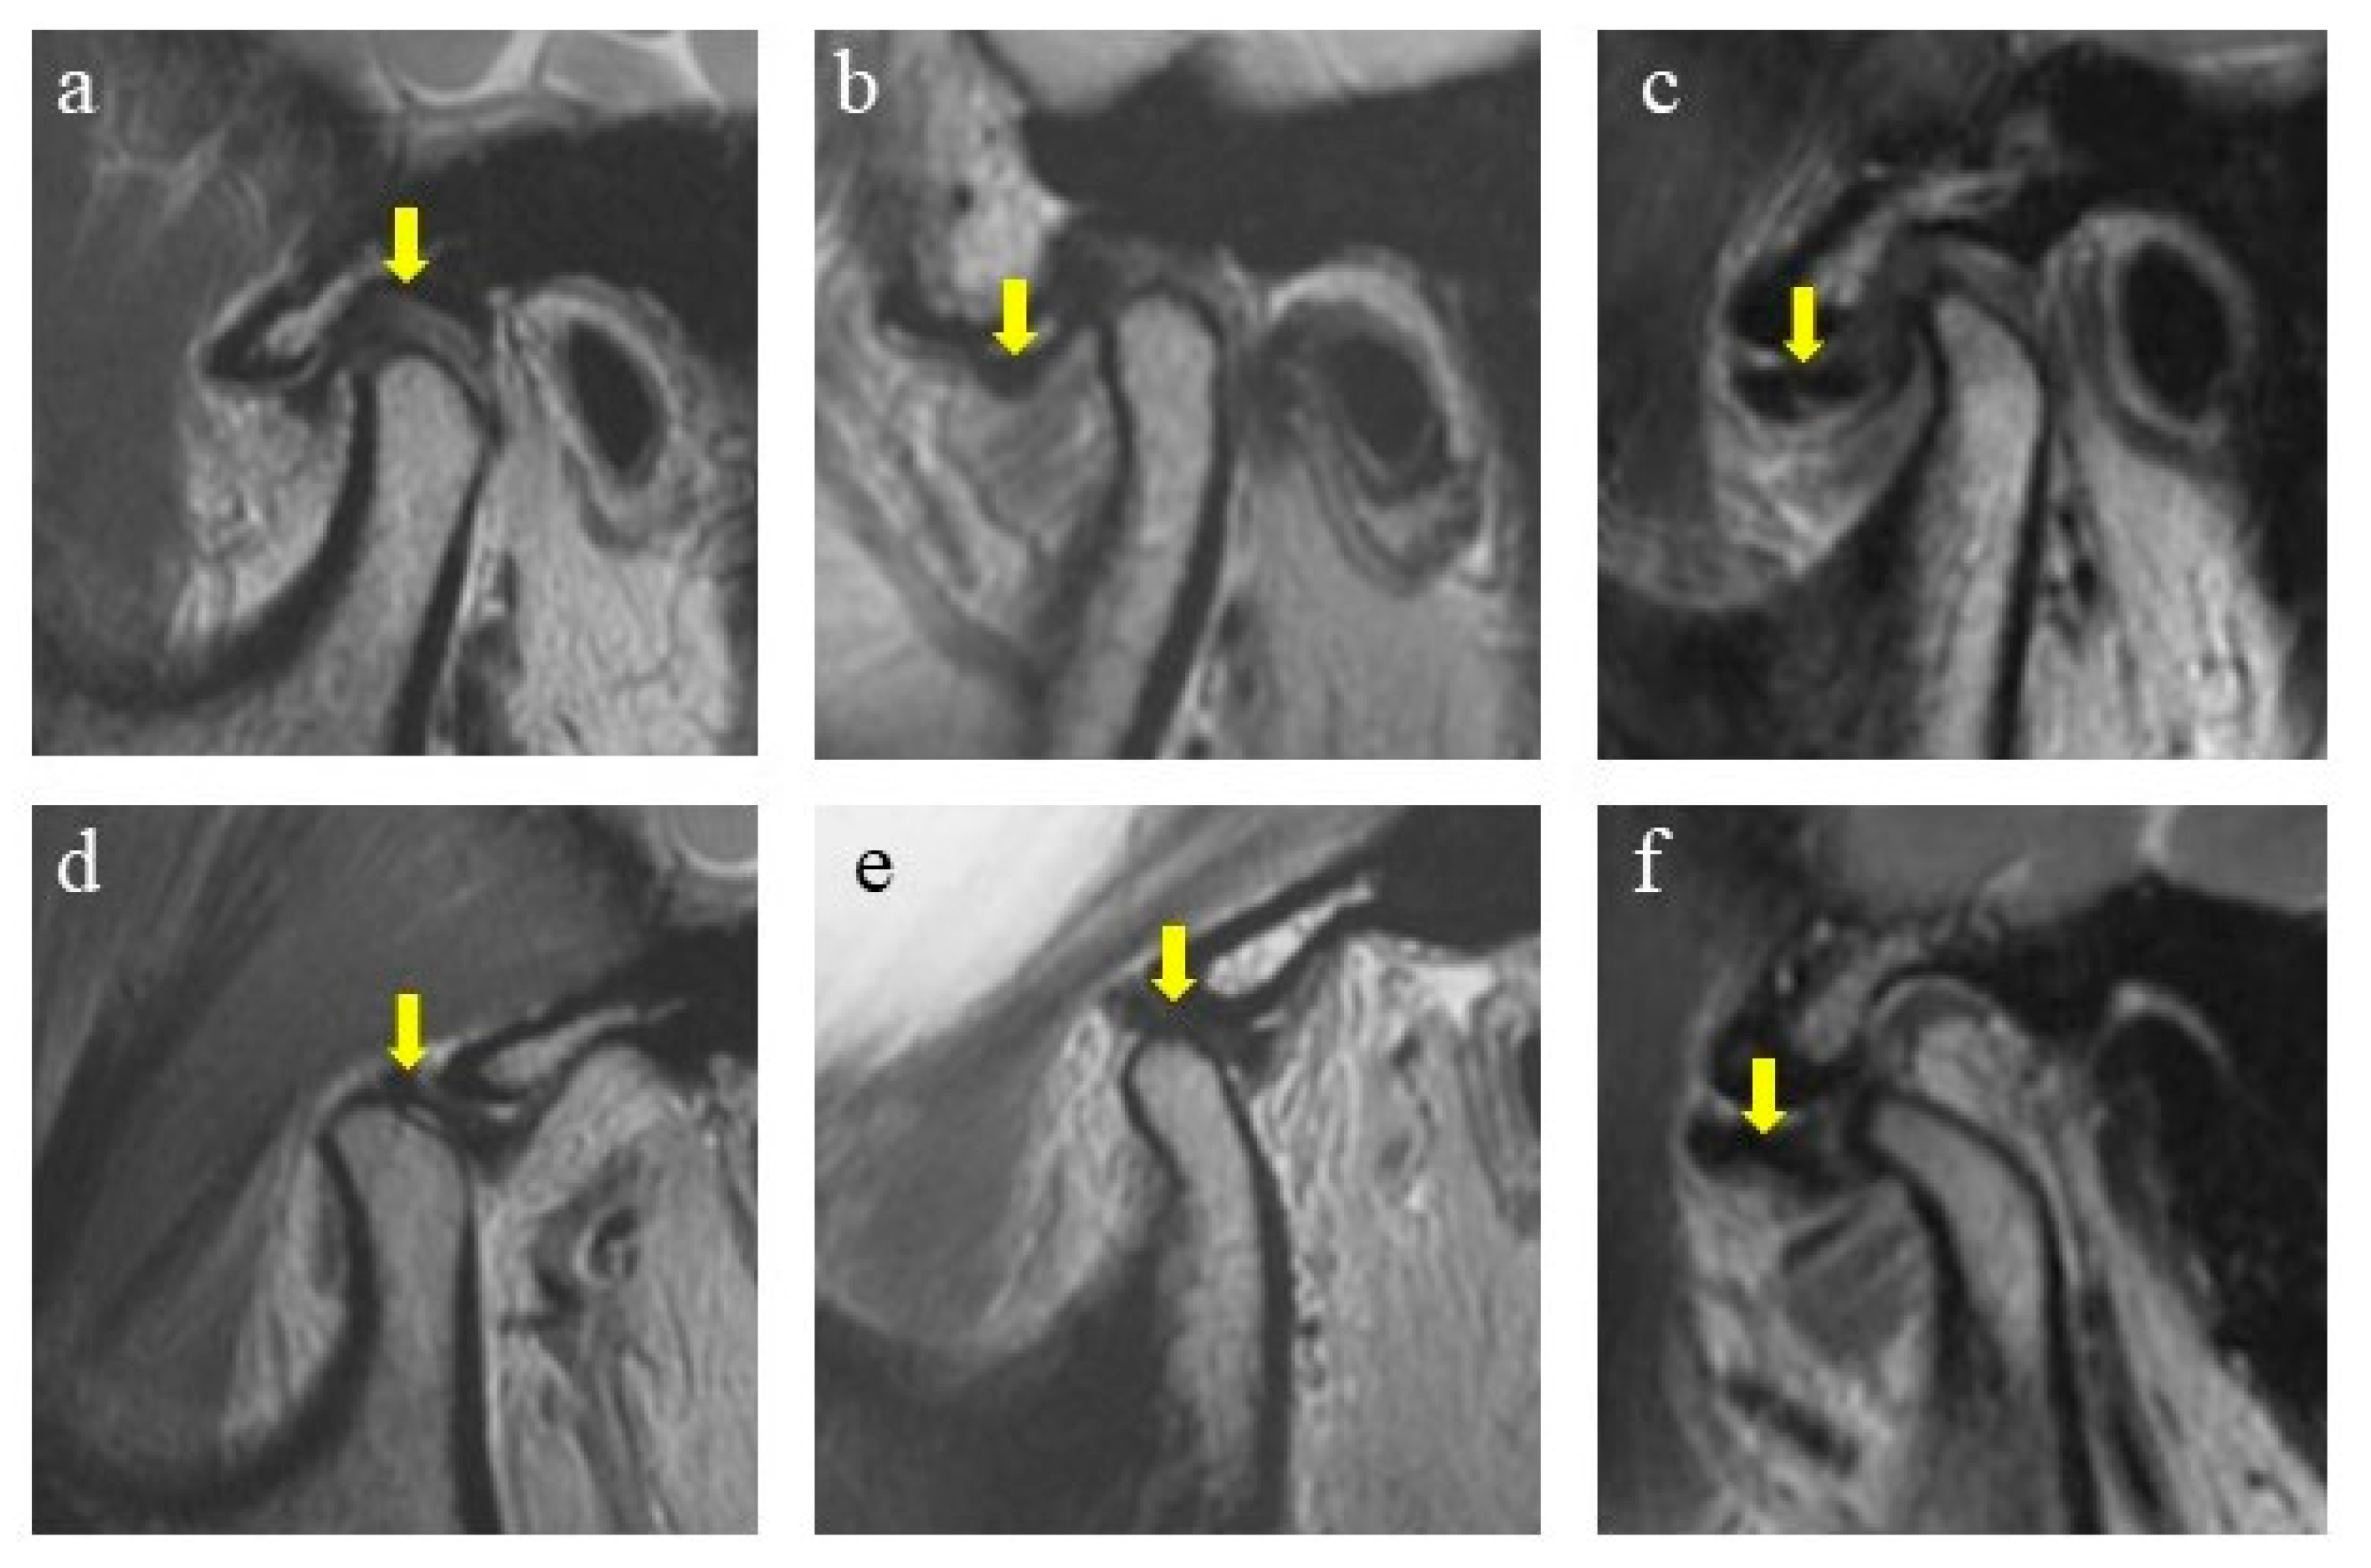

The MRIs were performed with a 1.5T MRI scanner (Philips, Amsterdam, The Netherlands) with a TMJ surface coil. To identify the disc position, T2-weighted imaging (T2WI) generated by a fast spin echo (FSE) sequence was examined. Parameter settings were: 2300 ms for repetition time; 45 ms for echo time; 3 mm for slice thickness; 0 mm for slice gap; 2 for number of excitations; 288 × 256 pixels for image matrix. The scanning included nonorthogonal sagittal and nonorthogonal coronal sections in the closed-mouth position and nonorthogonal sagittal sections in the open-mouth position. Patients assumed a supine position with the center of the coil positioned at a 10 mm anterior to the tragus. For the closed-mouth position, patients were instructed to occlude in the intercuspal position and hold the lips in a relaxed status. For the open-mouth position, patients were instructed to slowly reach maximum unassisted mouth opening (MMO), and then rubber pads with different thicknesses were applied to maintain the posture. MRI data were stored in DICOM format and observed with RadiAnt DICOM Viewer (Medixant, Poznan, Poland). The diagnosis of the subjects was categorized into 3 groups [18,19,20] (Figure 1). Two operators (C.Y. and X.X.) conducted the MRI diagnosis. The intra-observer and inter-observer reliability was verified before the study with a kappa coefficient >0.85.

Figure 1.

Diagnosis of disc displacements in MRIs. (a) Normal, in closed-mouth position; (b) DDwR, in closed-mouth position; (c) DDwoR, in closed-mouth position; (d) normal, in open-mouth position; (e) DDwR, in open-mouth position; (f) DDwoR, in open-mouth position. Arrow shows the position of the articular disc.

2.2.1. Normal Position

In the closed-mouth position, the intermediate zone of the articular disc was located between the posterior slope of the articular eminence and the anterior slope of the condyle head (defined as from 11:30 to 12:30 o’clock to the condyle head). In the open-mouth position, the intermediate zone was located between the top of the condyle head and the articular eminence. Subjects with articular discs of both sides in the normal position were assigned to the normal group.

2.2.2. Disc Displacement with Reduction (DDwR)

In the closed-mouth position, the intermediate zone of the articular disc was anteriorly displaced relative to the anterior slope of the condyle head (defined as before 11:30 o’clock to the condyle head). In the open-mouth position, the intermediate zone was reduced to the top of the condyle head and articular eminence. Subjects diagnosed with bilateral DDwR or unilateral DDwR with the other in the normal position were assigned to the DDwR group.

2.2.3. Disc Displacement without Reduction (DDwoR)

In the closed-mouth position, the intermediate zone of the articular disc was anteriorly displaced relative to the anterior slope of the condyle head. In the open-mouth position, the intermediate zone was still anteriorly displaced, which indicated no reduction. Subjects diagnosed with bilateral DDwoR or unilateral DDwoR, with or without DDwR for the other side, were assigned to the DDwoR group.